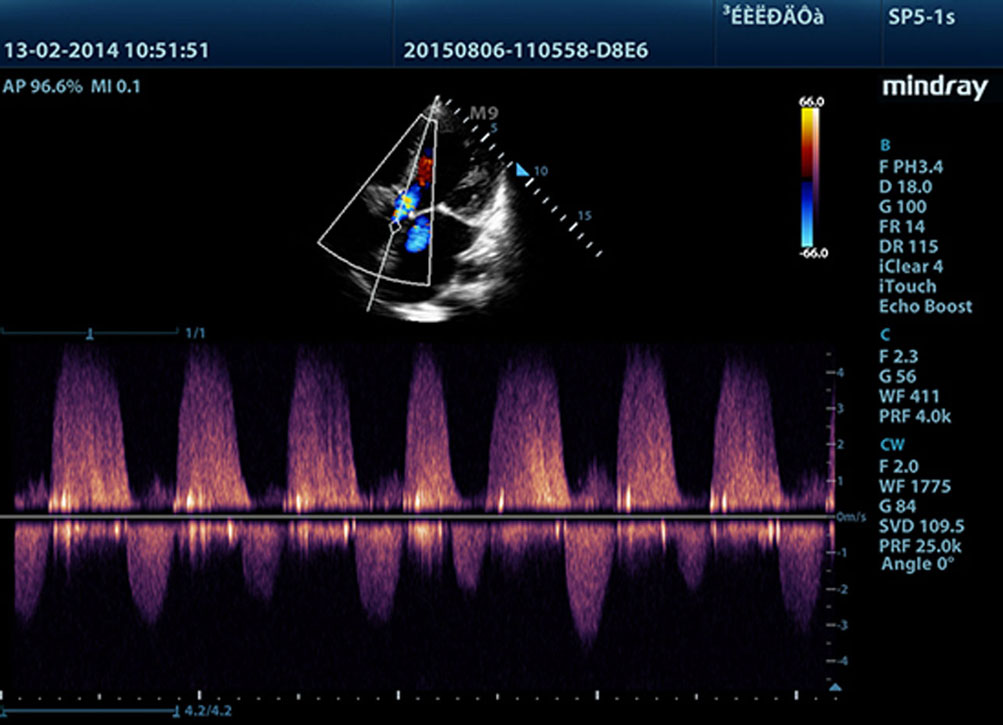

TDI

Met Tissue Doppler Imaging kunt u plaatselijke myocardiale beweging en functie kwantitatief evalueren, middels verschillende TDI modi voor snellere en directe diagnoses.